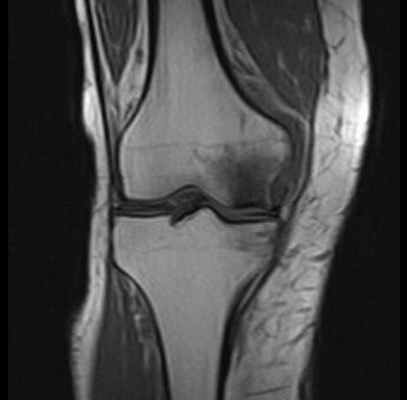

МРТ при некрозе костей колена. Нормальная ширина суставной щели, суставный хрящ ещё не поврежден. Отчетливое изображение некроза внутреннего мыщелка бедренной кости. © Prof. Dr. med. Sven Ostermeier

При недостаточном кровоснабжении костей погибают отдельные костные клетки. Таким образом некроз кости (Болезнь Альбека) означает потерю костного вещества в коленном суставе. Другими словами, остеонекроз — это отмирание костных структур.

На ранней стадии Болезнь Альбека можно диагностировать при помощи магнитно-резонансной томографии МРТ, которая показывает характерную, болезненную отечность. Измерение плотности костей необходимо для исключения остеопороза всей костной системы человека.